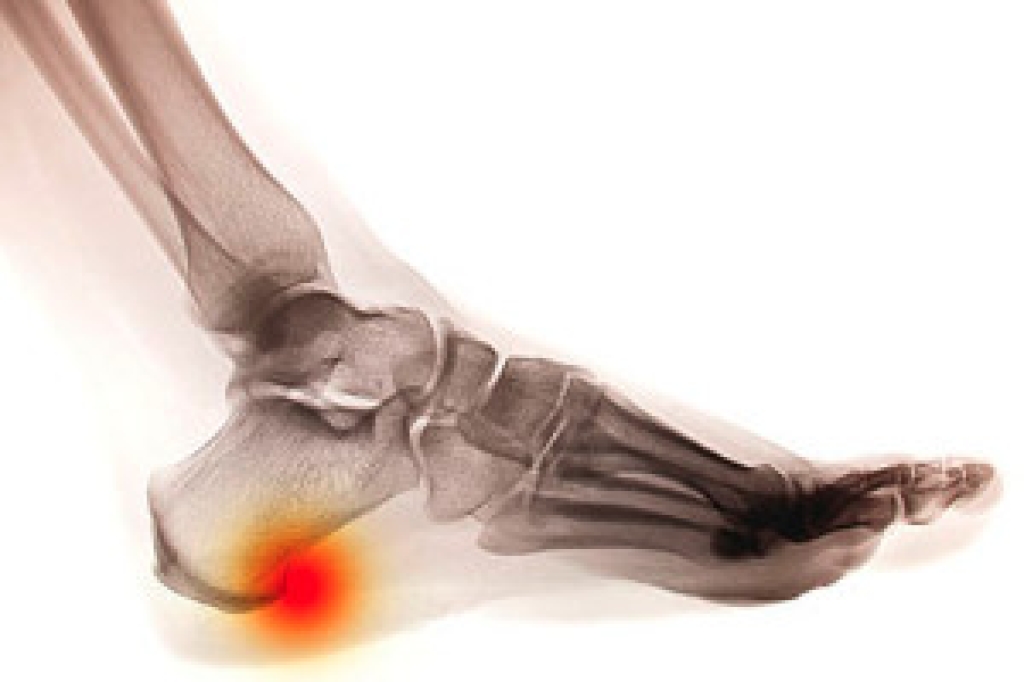

Ingrown toenails occur when the edge of the toenail grows into the surrounding skin, often affecting the big toe. This common condition can be caused by trimming toenails too short, wearing tight shoes, injury, or a natural curve in the nail. Symptoms include redness, swelling, pain along the nail edge, and sometimes drainage or infection, if left untreated. The area may feel tender to the touch and become increasingly painful when walking or wearing shoes. A podiatrist can diagnose an ingrown toenail with a simple exam. Treatment may involve gently lifting the nail edge, removing a portion of the nail, or prescribing antibiotics if an infection is present. In recurring cases, a minor procedure can permanently remove part of the nail to prevent future problems. Proper nail care and footwear recommendations can also help prevent recurrence. If you have developed an ingrown toenail, it is suggested that you promptly schedule an appointment with a podiatrist who can effectively treat this condition.

Ingrown toenails are caused when the corner or side of a toenail grows into the soft flesh surrounding it. They often result in redness, swelling, pain, and in some cases, infection. This condition typically affects the big toe and may recur if it is not treated properly.

Some symptoms of ingrown toenails are redness, swelling, and pain. In rare cases, there may be a yellowish drainage coming from the nail.

Ignoring an ingrown toenail can have serious complications. Infections of the nail border can progress to a deeper soft-tissue infection, which can then turn into a bone infection. You should always speak with your podiatrist if you suspect you have an ingrown toenail, especially if you have diabetes or poor circulation.